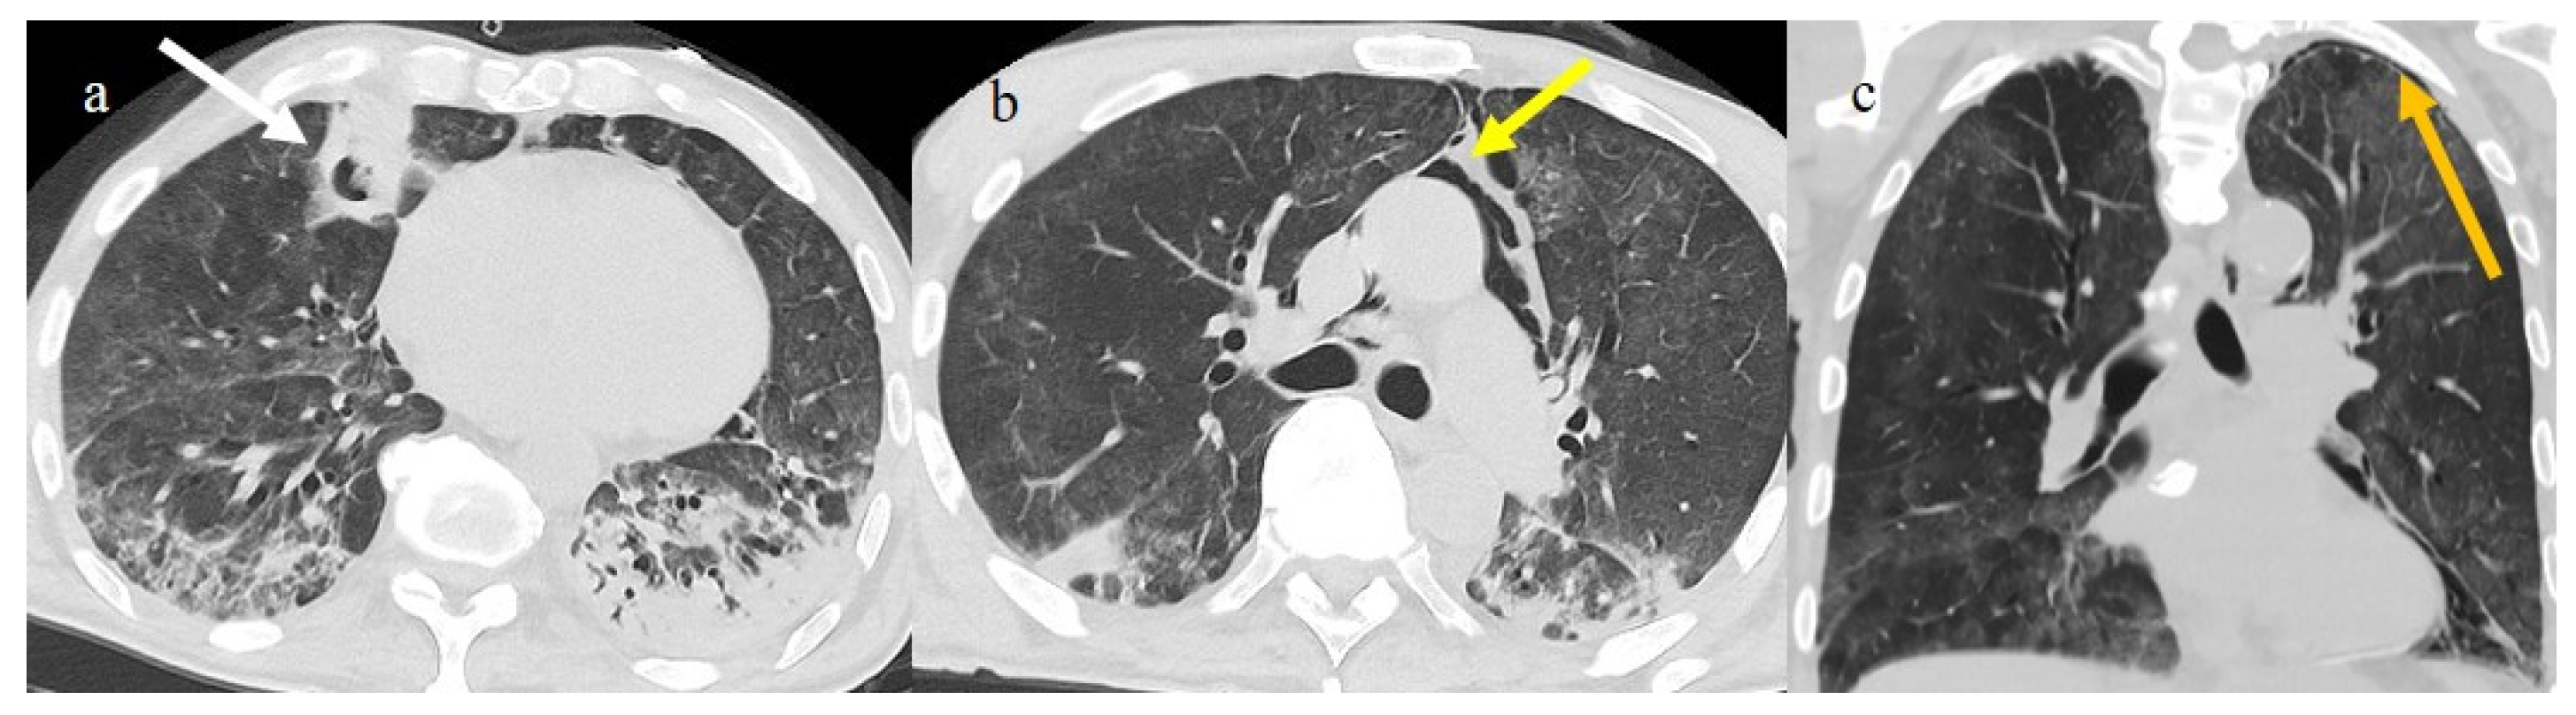

3.3.2. Pneumomediastinum and Pneumothorax

Pneumomediastinum (PMS) is the presence of air in the mediastinum. PMS has been identified as a complication in lung infections such as influenza and previous coronavirus infections such as SARS-CoV-1 and Middle East respiratory syndrome (MERS). It appears to be a marker of severe COVID-19 pneumonitis [110,111]. This condition can be spontaneous or secondary. The secondary form is the most common, with high incidence during the first three waves of the pandemic in critically ill patients (Figure 15) and may be related to mechanical ventilation in patients with ARDS receiving high positive pressure ventilation (PPV) [110,111,112,113,114,115,116]. Pneumothorax (PNX) was found to co-exist with PMS in 40.3% of cases [110]. Several studies have reported that the incidence of barotrauma in COVID-19 patients was 14% [114,115]. However, Martinelli et al. [117] reported a much higher incidence placing it at 25%. Subcutaneous emphysema is usually associated with PMS and PTX. The spontaneous forms of PMS and PNX have no apparent causes; however, several predisposing and precipitating factors have been identified, such as asthma, respiratory infections, lung cysts, inhaled drug use, corticosteroids, and the inhalation of irritants, as well as several anatomical predisposing alterations, including tracheomalacia [111,118,119,120,121,122]. Lung damage with alveolar rupture in COVID-19 infections can probably lead to interstitial pneumothorax, which can cause spontaneous PMS related to the Macklin effect [110,111,118,119,120,121,122]. In severe cases of COVID-19 pneumonia, parenchymal destruction can lead to the formation of cavitation and lung cysts, which can cause PTX and PMS after rupture [111,118,119,120,121,122].

The spontaneous forms of PTX and PMS occurred in 1–2% of all COVID-19 pneumonia patients [118,122]. In rare cases, spontaneous PMS was associated with PTX [123]. The prevalence of these conditions increased during the second wave of the pandemic with the increasing use of oxygen through non-invasive ventilation and steroid therapy [118,121,122,123,124,125,126]. The high airway pressures delivered by these modalities of respiration probably supported the spontaneous rupture of fragile small airways infected by the virus (Figure 17 and Figure 18).

Figure 17.

Chest CT during the second pandemic wave (November 2020) in a 71-year-old patient with a history of diabetes mellitus. The patient was under non-mechanical ventilation and developed a cavity lesion (white arrow) in image (a), pneumomediastinum (yellow arrow) in image (b), and a small pneumothorax (orange arrow) as visualized in image (c).

Figure 18.

Chest CT during the second pandemic wave (November 2020) in a 40-year-old patient without known comorbidities. The patient was under non-mechanical ventilation with CPAP and developed pneumomediastinum (yellow arrow), as visualized on axial plane in image (a) (on lung window) and in image (b) mediastinal window; severe pneumonia with consolidations is also visualized in image (a).

However, Palumbo et al. [126] hypothesized that the increased incidence of SMPS and SPTX during the second pandemic wave was caused by the increased use of dexamethasone, which might have induced lung frailty. Rare cases of SPMS were usually reported during the Omicron wave [127].